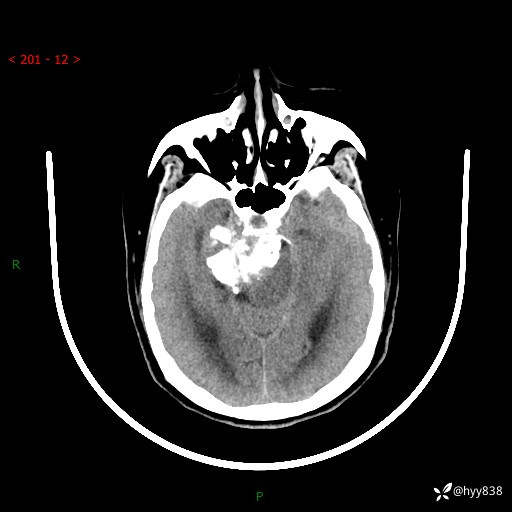

52岁/女,发现颅内占位4天。颅底钙化性肿块---结果公布~

颅脑CT平扫